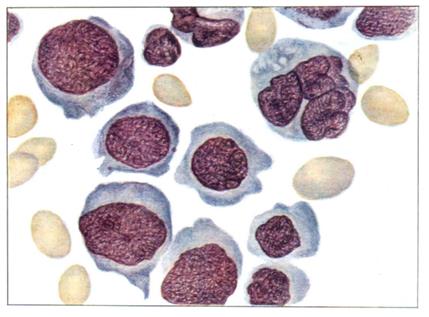

Мегалобласты в костном мозгу при пернициозной анемии

Рис. 22

Поступая в кровь, они формируют специфическую гематологическую картину анемии: наличие гигантских гиперхроматированных макроцитов. Нестабильная ДНК образует структуры типа колец Кабо и телец Жолли. Анемия сопровождается лейко - и тромоцитопенией, причем полиморфно-ядерные лейкоциты имеют гиперсегментированные ядра, а тромбоциты - гигантские размеры (рис.22, 23).

Рис. 23. Пернициозная анемия. Тяжелый рецидив болезни (слева): в поле зрения видны мегалобласты различных генераций, мегалоциты, эритроциты с ядерными дериватами (кольца Кабо, тельца Жолли) и базофильной пунктацией, характерный полисегментоядерный нейтрофил. Стадия ремиссии (справа): макроанизоцитоз эритроцитов, полисегментоядерный нейтрофил.